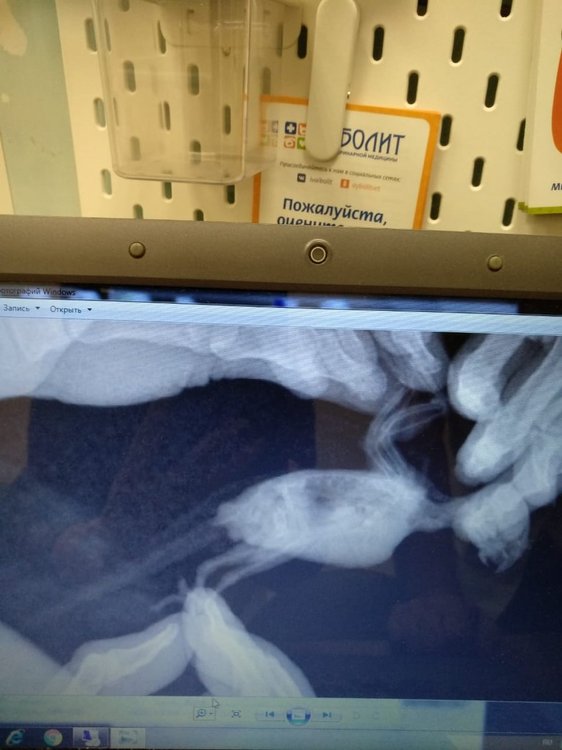

Добрый день! Все такт поехали мы к орнитологу в иваново.

Сделали рентген, врач осмотрел птичку. Поставил предварительный диагноз артроз. Подагру пока не ставит. На рентгене - отложения солей. Что удивительно, отложений больше на той лапке, на которую сейчас опирается больше. Сказал, что мы до этого все правильно лечились. Так что спасибо за советы!!! *THUMBS UP*

Разместите рентген, чтоб  @Zosia  посмотрела -- есть ли там артроз.

Вот наши рентгены. Только качество не очень.т.к. Фотка это